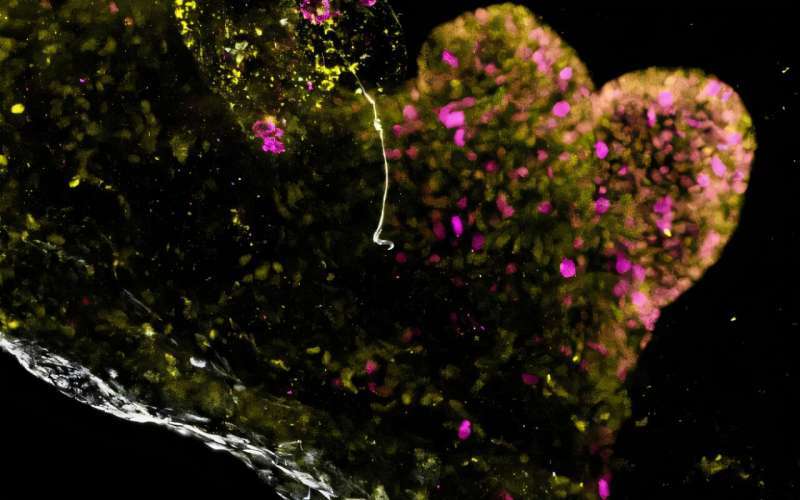

Imagine de imunofluorescenţă a regiunii antrale a unui assembloid multiregional obţinut din celule provenite de la pacienţi cu PMM2, care evidenţiază proliferarea excesivă a celulelor în lumenul assembloidului. Markerul de proliferare celulară KI67 este marcat în magenta, PDX1 în galben, iar mucina în alb. Credit: B. Jones, G. Benedetti et al., Nature Biomedical Engineering, 2026.